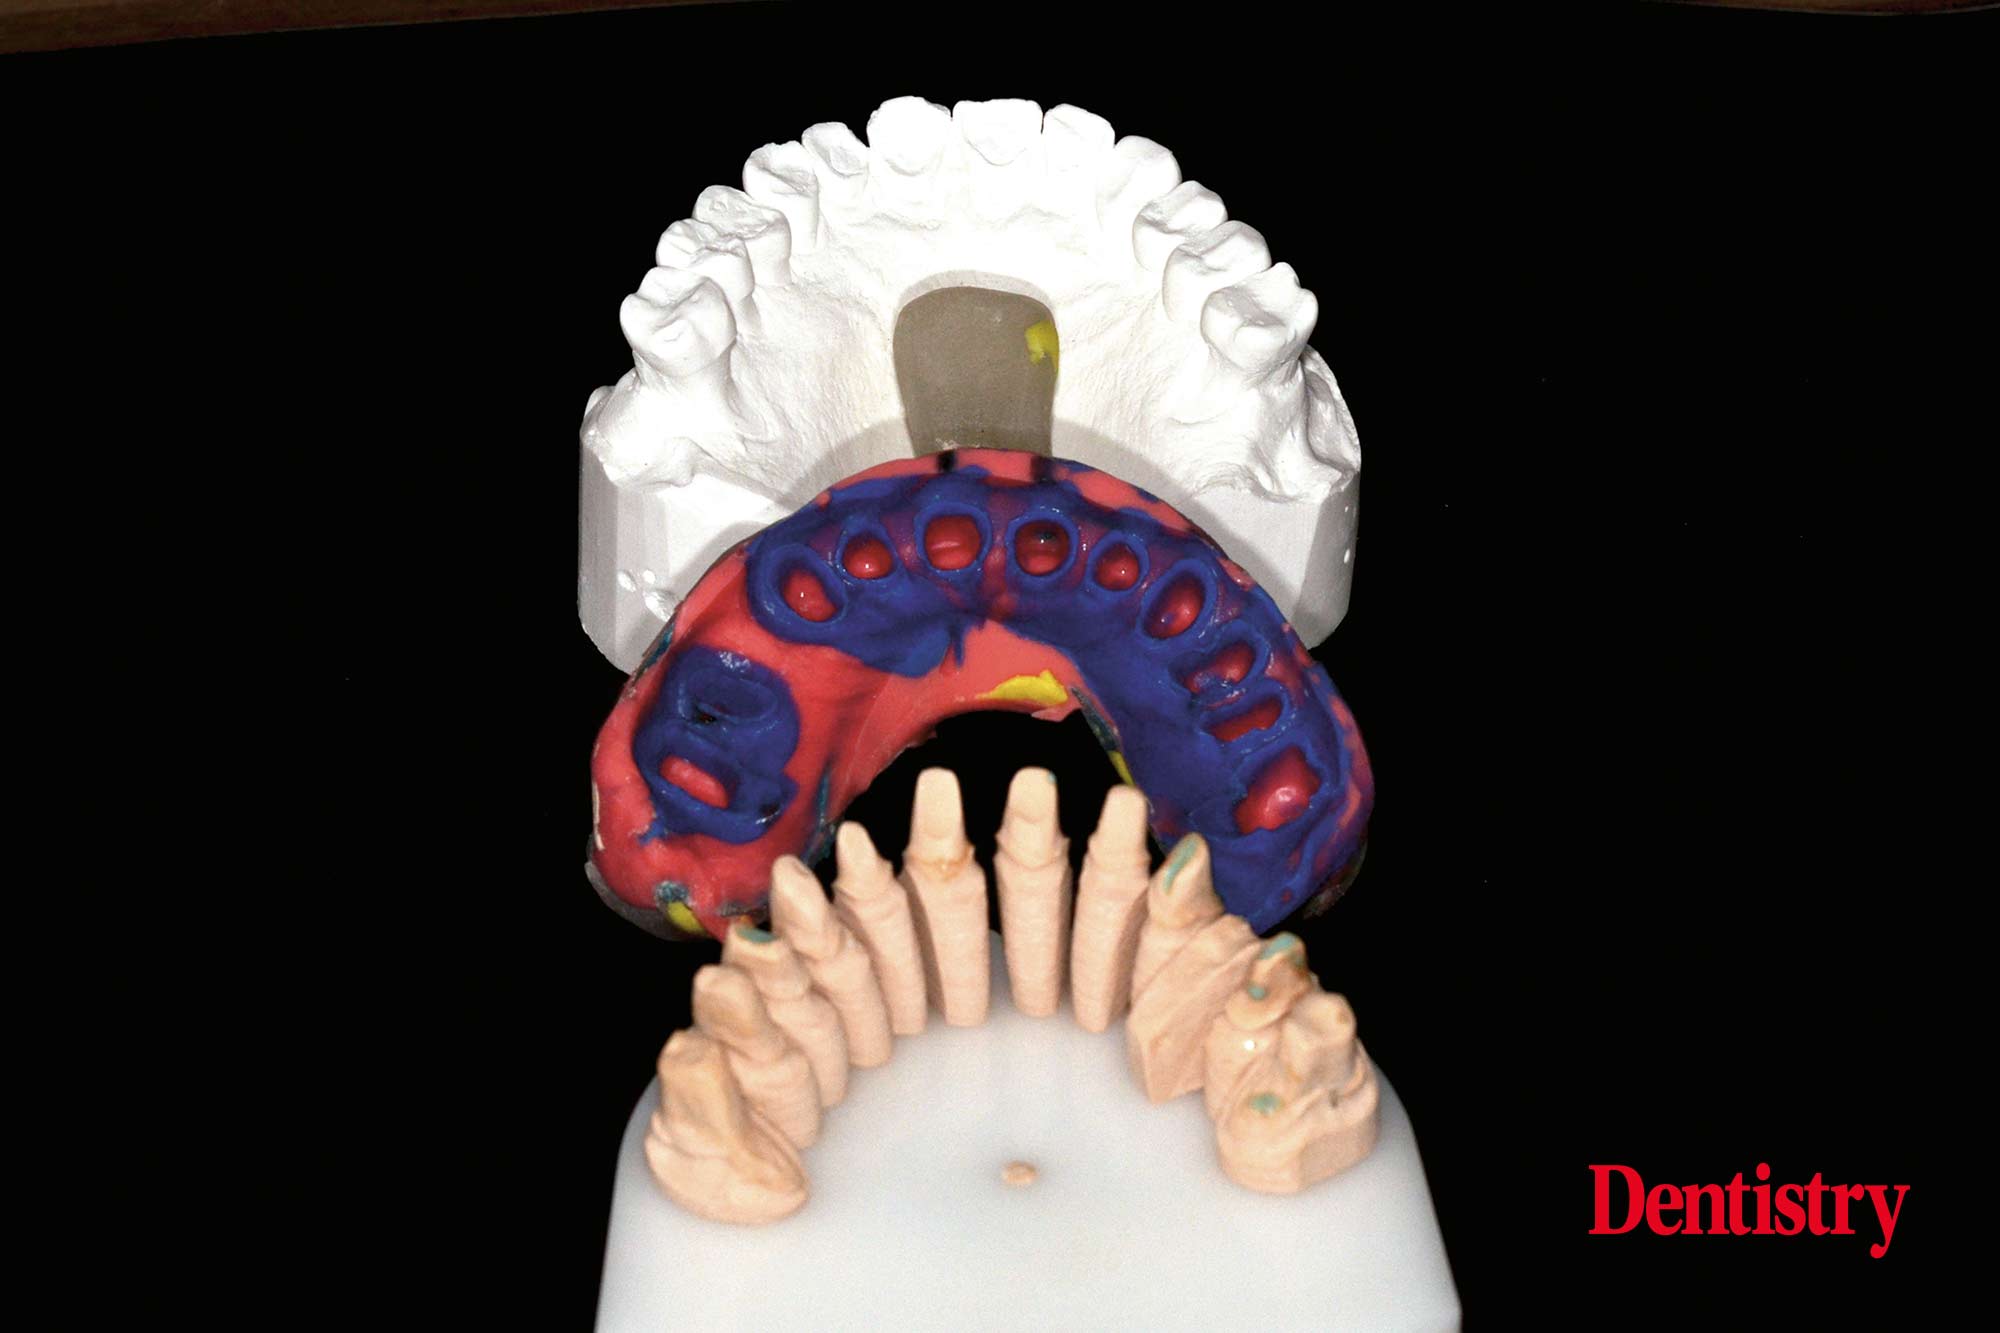

All teeth were prepared for full coverage crowns and then PVS impressions were taken utilising retraction cord. The models were poured (Figures 2a and 2b).